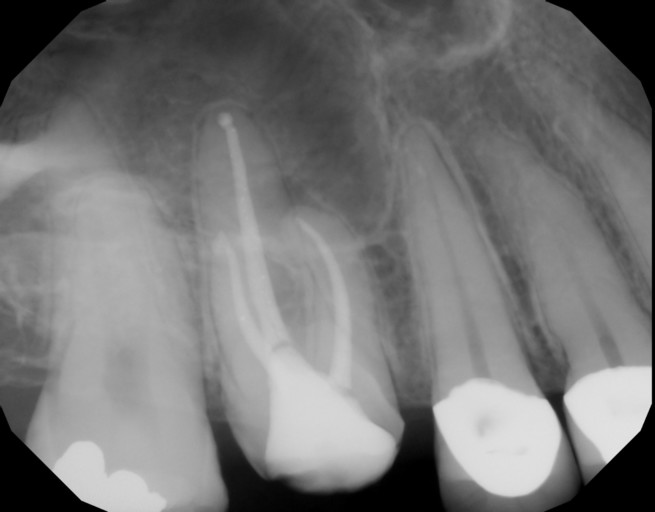

If My Front Tooth can be Salvaged.

Hi,I reinjured one of my front teeth that was previously injured after a fall and was pushed back in my mouth 1 yr ago. I had it positioned back into place, got a root canal done and had splinter over it. But 2 weeks ago I reinjured the tooth and it...